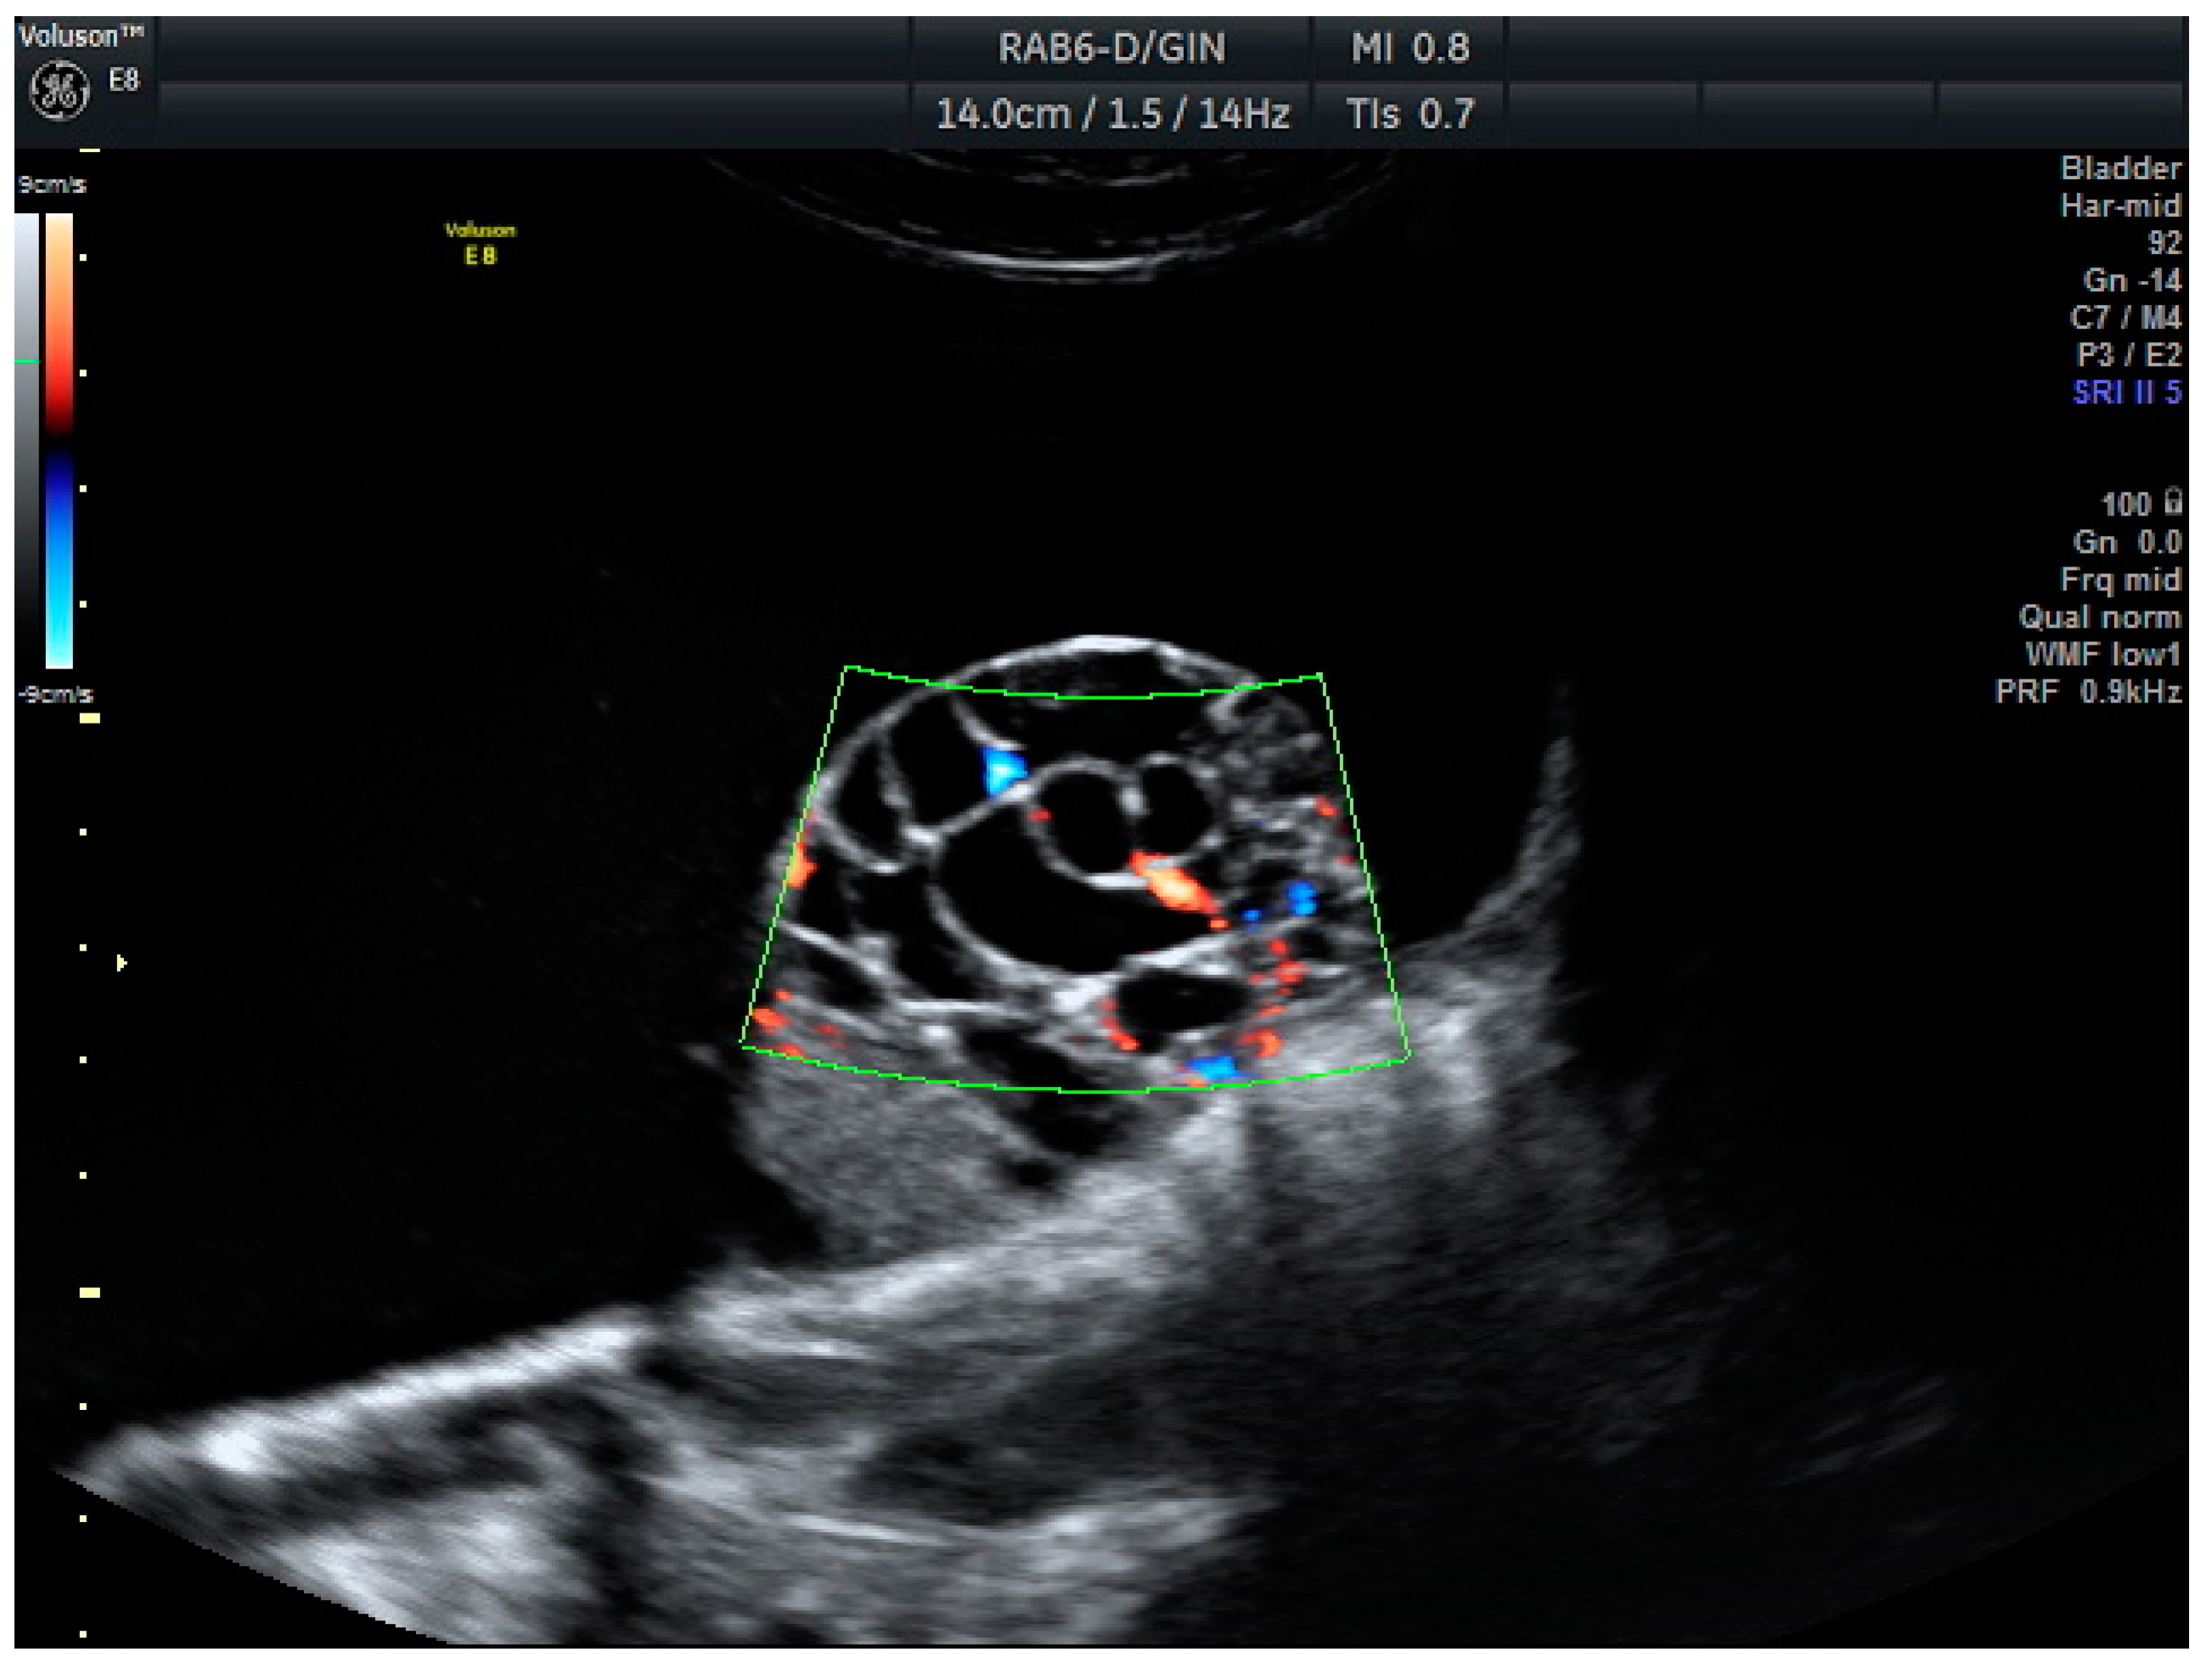

Figure 1.

Mucinous carcinoma: Unilocular cystic mass with a solid-cystic papilla inside, showing extensive vascularization (score color 4).